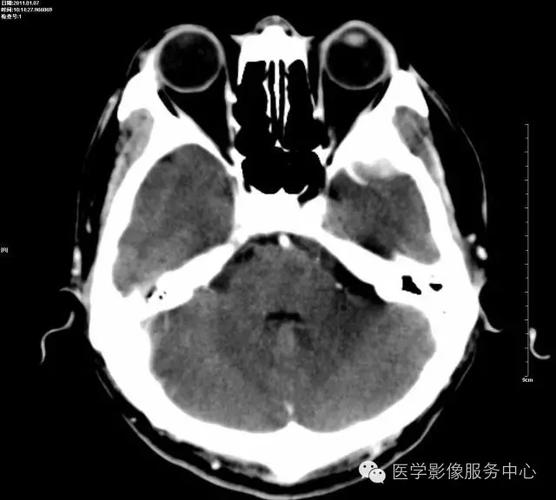

影像总结头颅ct基本知识与常见病变

脑部ct照片真实

头颅CT图片